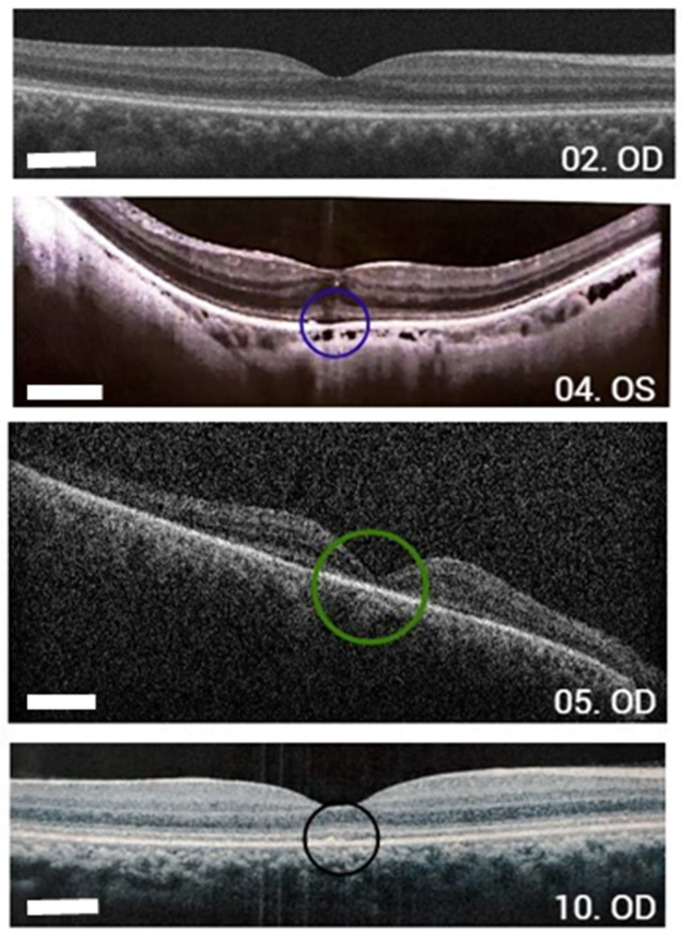

The anatomical and physiological similarities between human and canine eyes suggest that dogs may serve as a valuable model for studying retinopathies and developing future gene therapies. This study aims to evaluate the similarities and differences between humans with GUCY2D gene variants causing Leber's congenital amaurosis (LCA) and a group of German Spitz dogs with hereditary retinopathy due to variants in the same gene, to assess their potential as an animal model for gene therapy research. A review of medical records, genetic testing, and ophthalmological examinations was conducted, including data such as age, genotyping, fundus photography, visual acuity (VA), fundus autofluorescence, optical coherence tomography (OCT), and electroretinography (ERG). Both groups presented subtle fundus abnormalities and severely reduced or absent ERG responses. In humans, OCT scans revealed decreased retinal thickness and structural alterations in the outer retinal layers. Similarly, the affected dogs exhibited focal neurosensory retinal detachments. The German Spitz model with GUCY2D variants shows significant parallels in retinal structure and functional impairment and may represent a promising candidate for preclinical gene therapy studies for LCA.